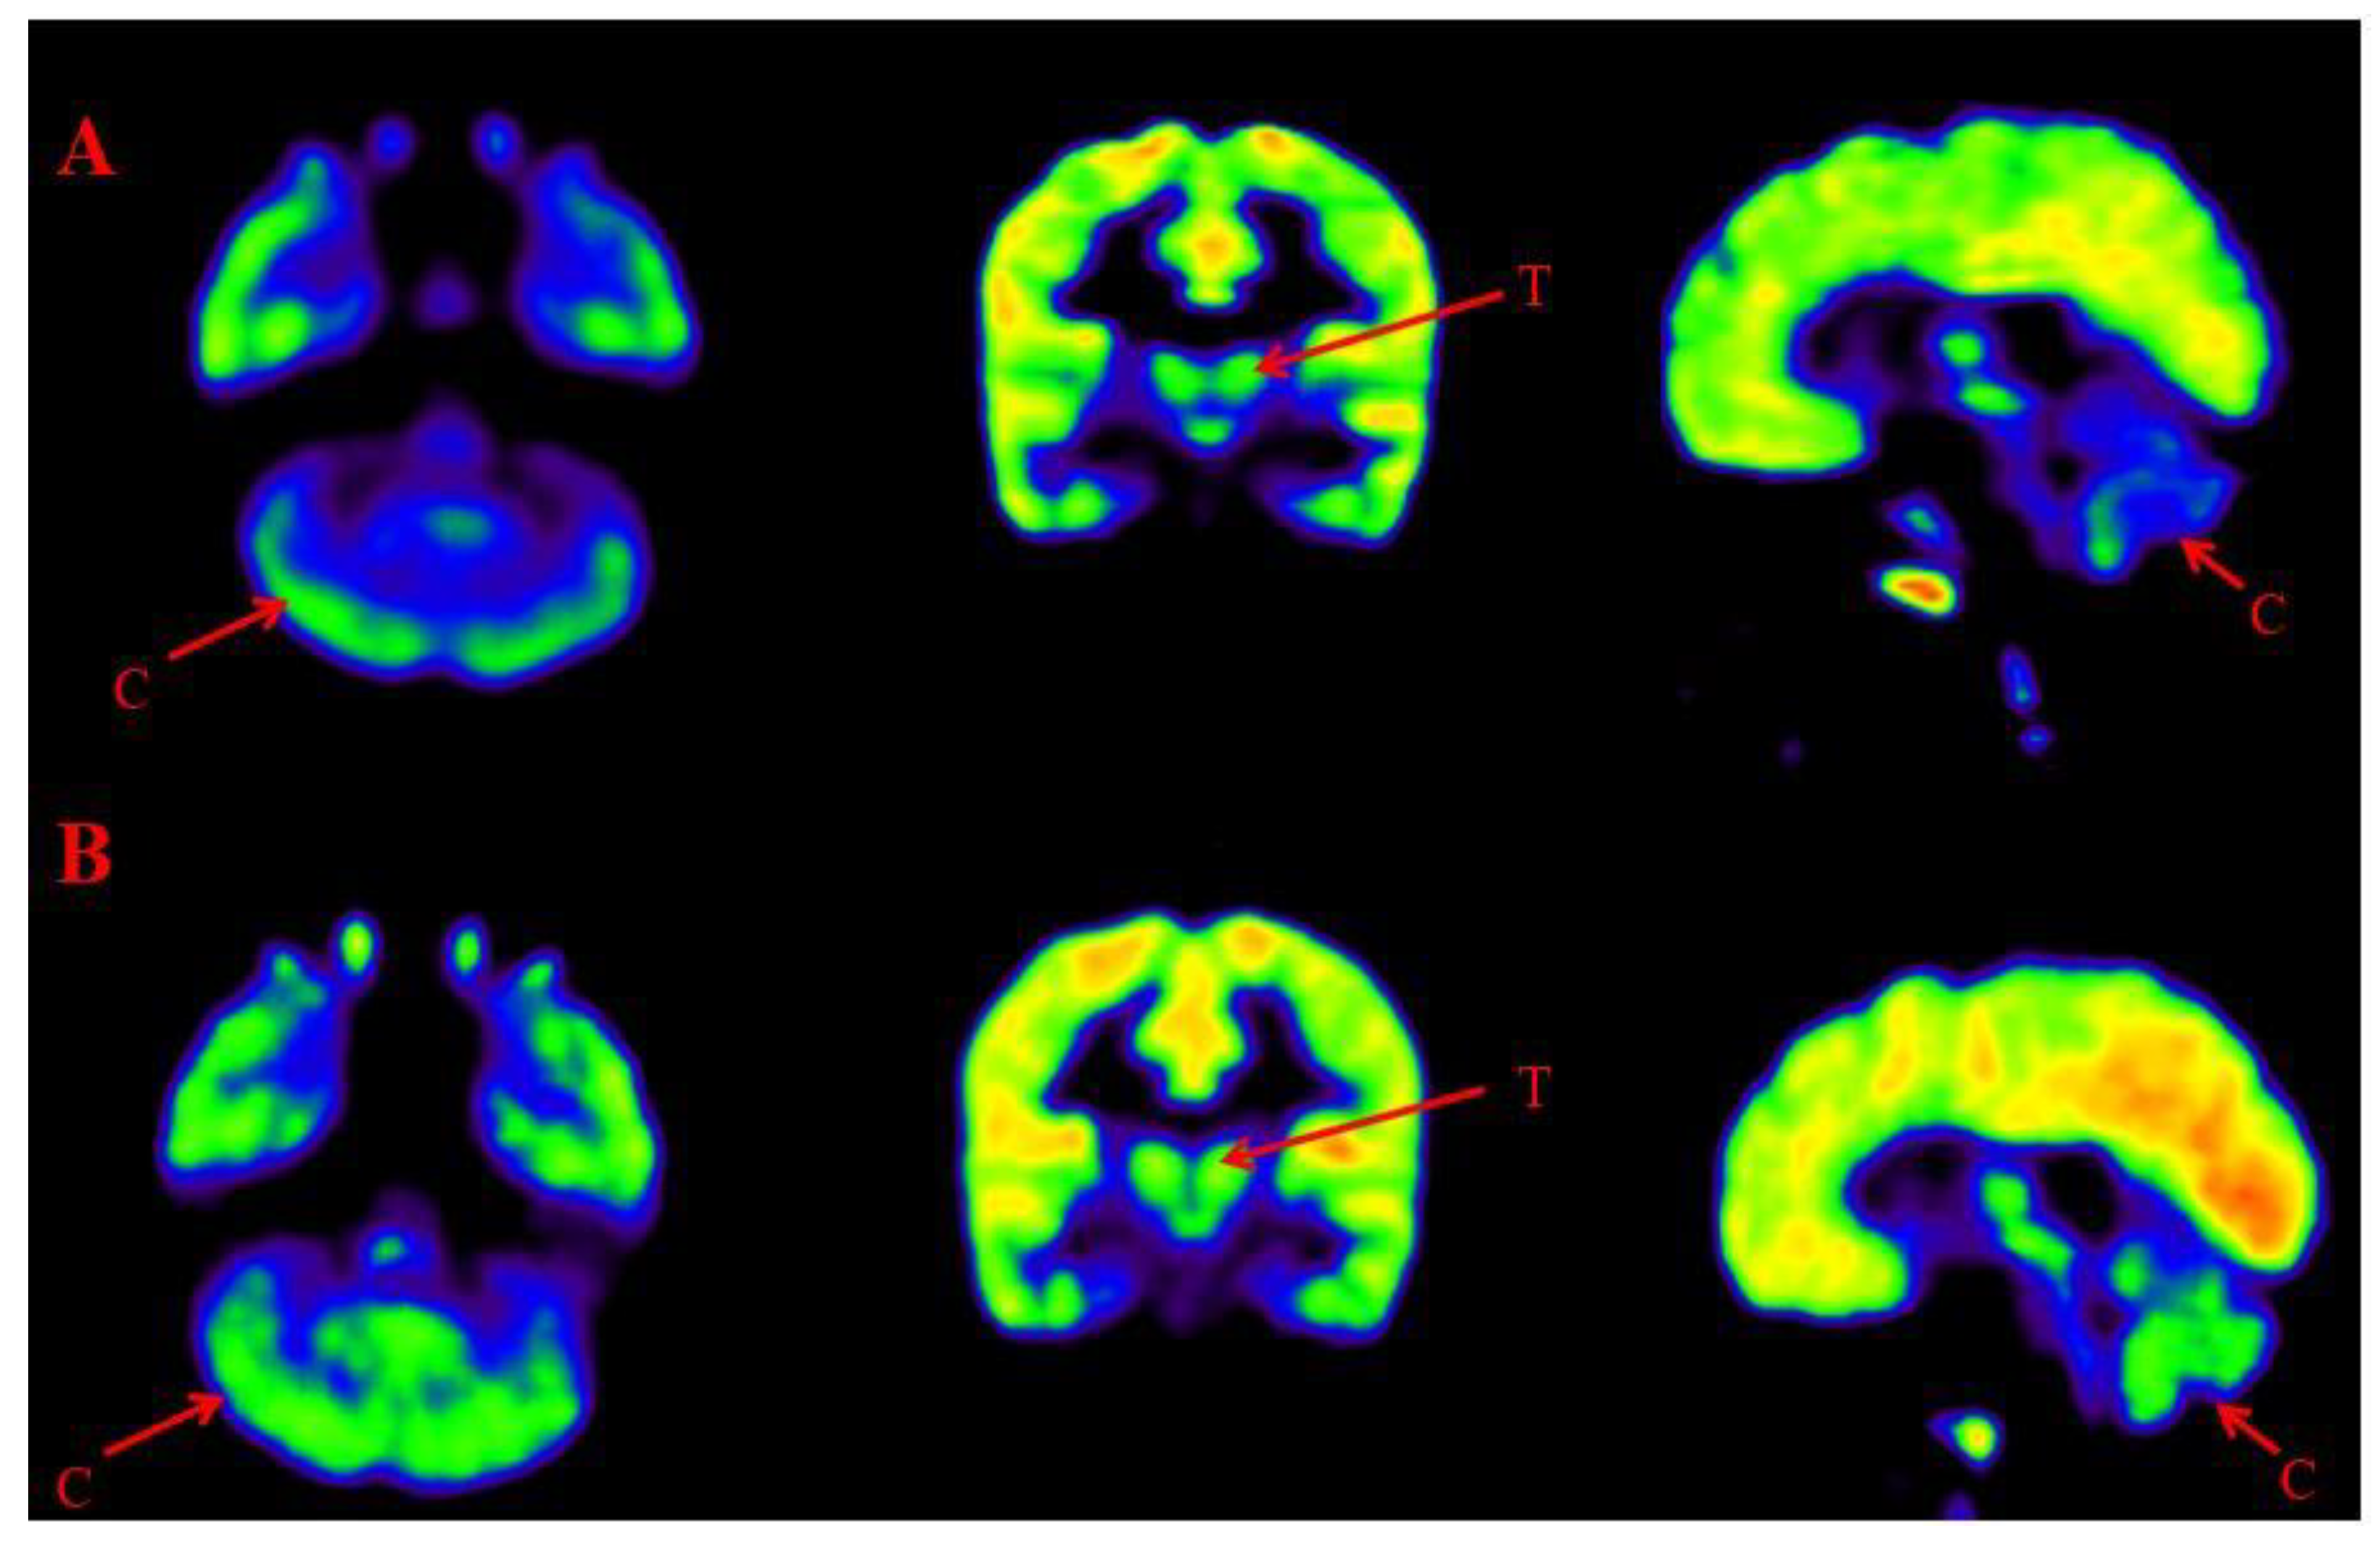

Comparison of Brain FDG PET scans performed before and after intervention was done to observe the metabolic changes in the brain after BMMNCs administration. 18-FDG PET scan shows glucose uptake in different brain areas and also depicts efficacy of treatment in ASD patients via change in metabolic rate [16]. A comparative PET CT scan was performed in 401 patients. Improved metabolism, reduction in percent hypometabolism, was observed in brain regions including amygdala, hippocampus, parahippocampal gyrus, caudate nucleus, cerebellum, mesial temporal lobe, thalamus, superior and middle temporal poles (Figure 6, Figure 7). The grading of these distinct nine regions showed statistically significant improvement on Wilcoxon’s signed rank test (p<0.05) after cell therapy.

Figure 7. Representative images of Comparative Brain FDG PET scan of ASD patients performed before and after Cell therapy. Top Row (A): Arrow marked blue areas represent hypometabolism. Bottom Row (B): Arrow marked green areas showing improved metabolism post Cell therapy. Cerebellum (C) and Thalamus (T).